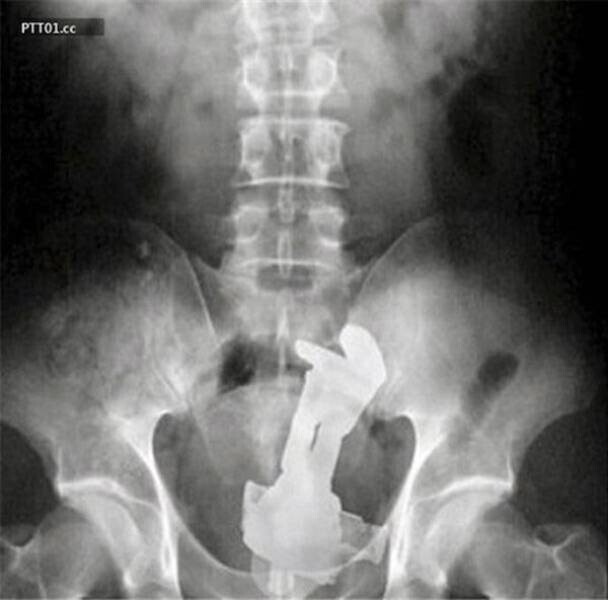

11. Гумовий кулак